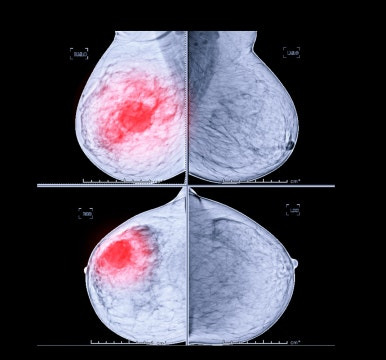

2. 그렇다면 유방암이란 무엇일까?

유방암은 여성들에게 가장 흔한 암 중 하나이며, 조기에 치료하면 5년 생존율이 95% 이상으로 높은 편입니다. 하지만 전이와 재발이 쉬운 암종이기 때문에 수술 이후 지속적인 면역력 관리가 필수적인 암종이죠.

유방암 환자들은 수술 후 방사선 치료, 항암제 치료 등을 진행하는데, 이 과정에서 신체적 부담과 면역력 저하가 발생할 수 있습니다. 따라서 면역력을 증진시키고, 항암 치료로 인한 부작용을 최소화하기 위한 체계적인 관리가 필요합니다.